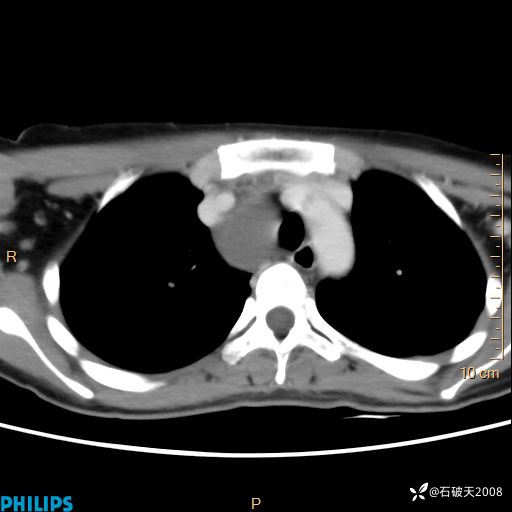

影像诊断要密切结合临床,真的很有必要(病理已公布)

女 21岁 主 诉:发现右侧颈部肿物18年余。

现病史:18年余前患者无明显诱因发现颈部偏右侧有一肿物,具体大小不明确,咳嗽、憋气时肿物增大,局部无疼痛,无吞咽不适,无胸闷及呼吸困难,至当地医院检查考虑良性病变(具体不详)并未做特殊处理,现患者自觉肿物随年龄增长而进一步变大,今日至我院行颈部CT平扫+增强提示:1.右侧颈根部、锁骨上窝及纵隔内异常密度影,考虑良性病变,淋巴管瘤?囊肿?请结合临床。2.双侧颈部小淋巴结。建议结合临床及其他相关检查。现为行进一步治疗,门诊以“颈部局部肿物”为诊断收住我科,发病来患者神志清,精神可,饮食睡眠可,大小便正常,体重无下降。

动脉期